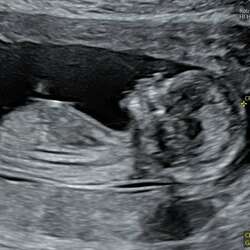

Pff moeten zo moeten we ons echt over alles druk maken馃檲 ik zou persoonlijk hem wat minder warm zetten dan normaal. Er zitten nog wel wat laagjes tussen de stoelleuning en de baarmoeder. Misschien dat het wat meer effect heeft op de temperatuur van het vruchtwater als we wat verder zijn, maar tegen dit tijd is het waarschijnlijk zo warm dat we geen stoelverwarming meer willen!